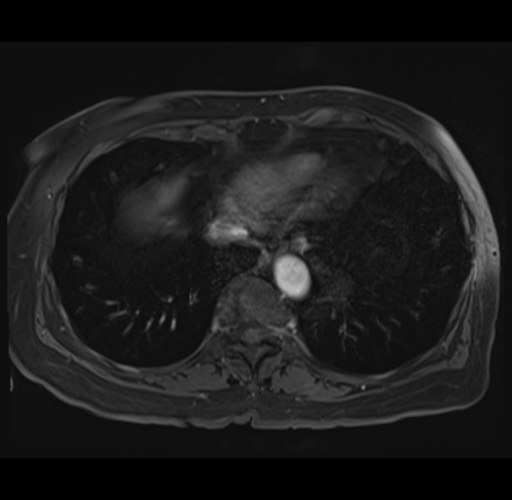

MRI T1